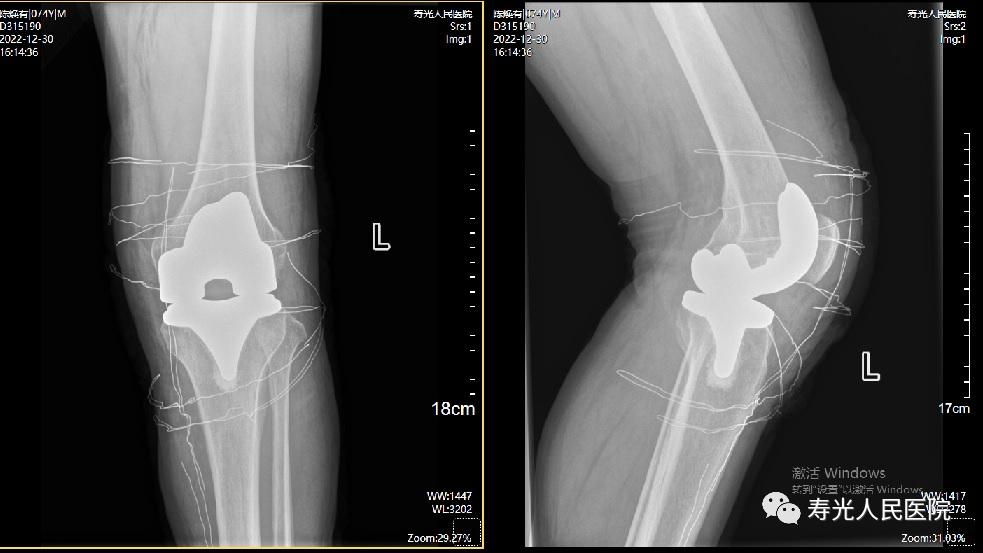

术后影像